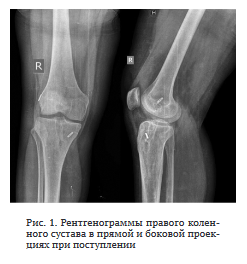

Первый этап лечения. Ревизия правого коленного сустава; удаление трансплантата ПКС; дебридмент;

УЗ кавитация раны; пластика дефектов костным цементом с ванкомицином (рис. 2). Результаты интраоперационного микробиологического исследования — МК8Е 103 КОЕ/мл. Интраоперационная кровопотеря составила 100 мл, гемотрансфузию не проводили. Рана зажила первичным натяжением. Дренаж удален на третьи сутки после операции.